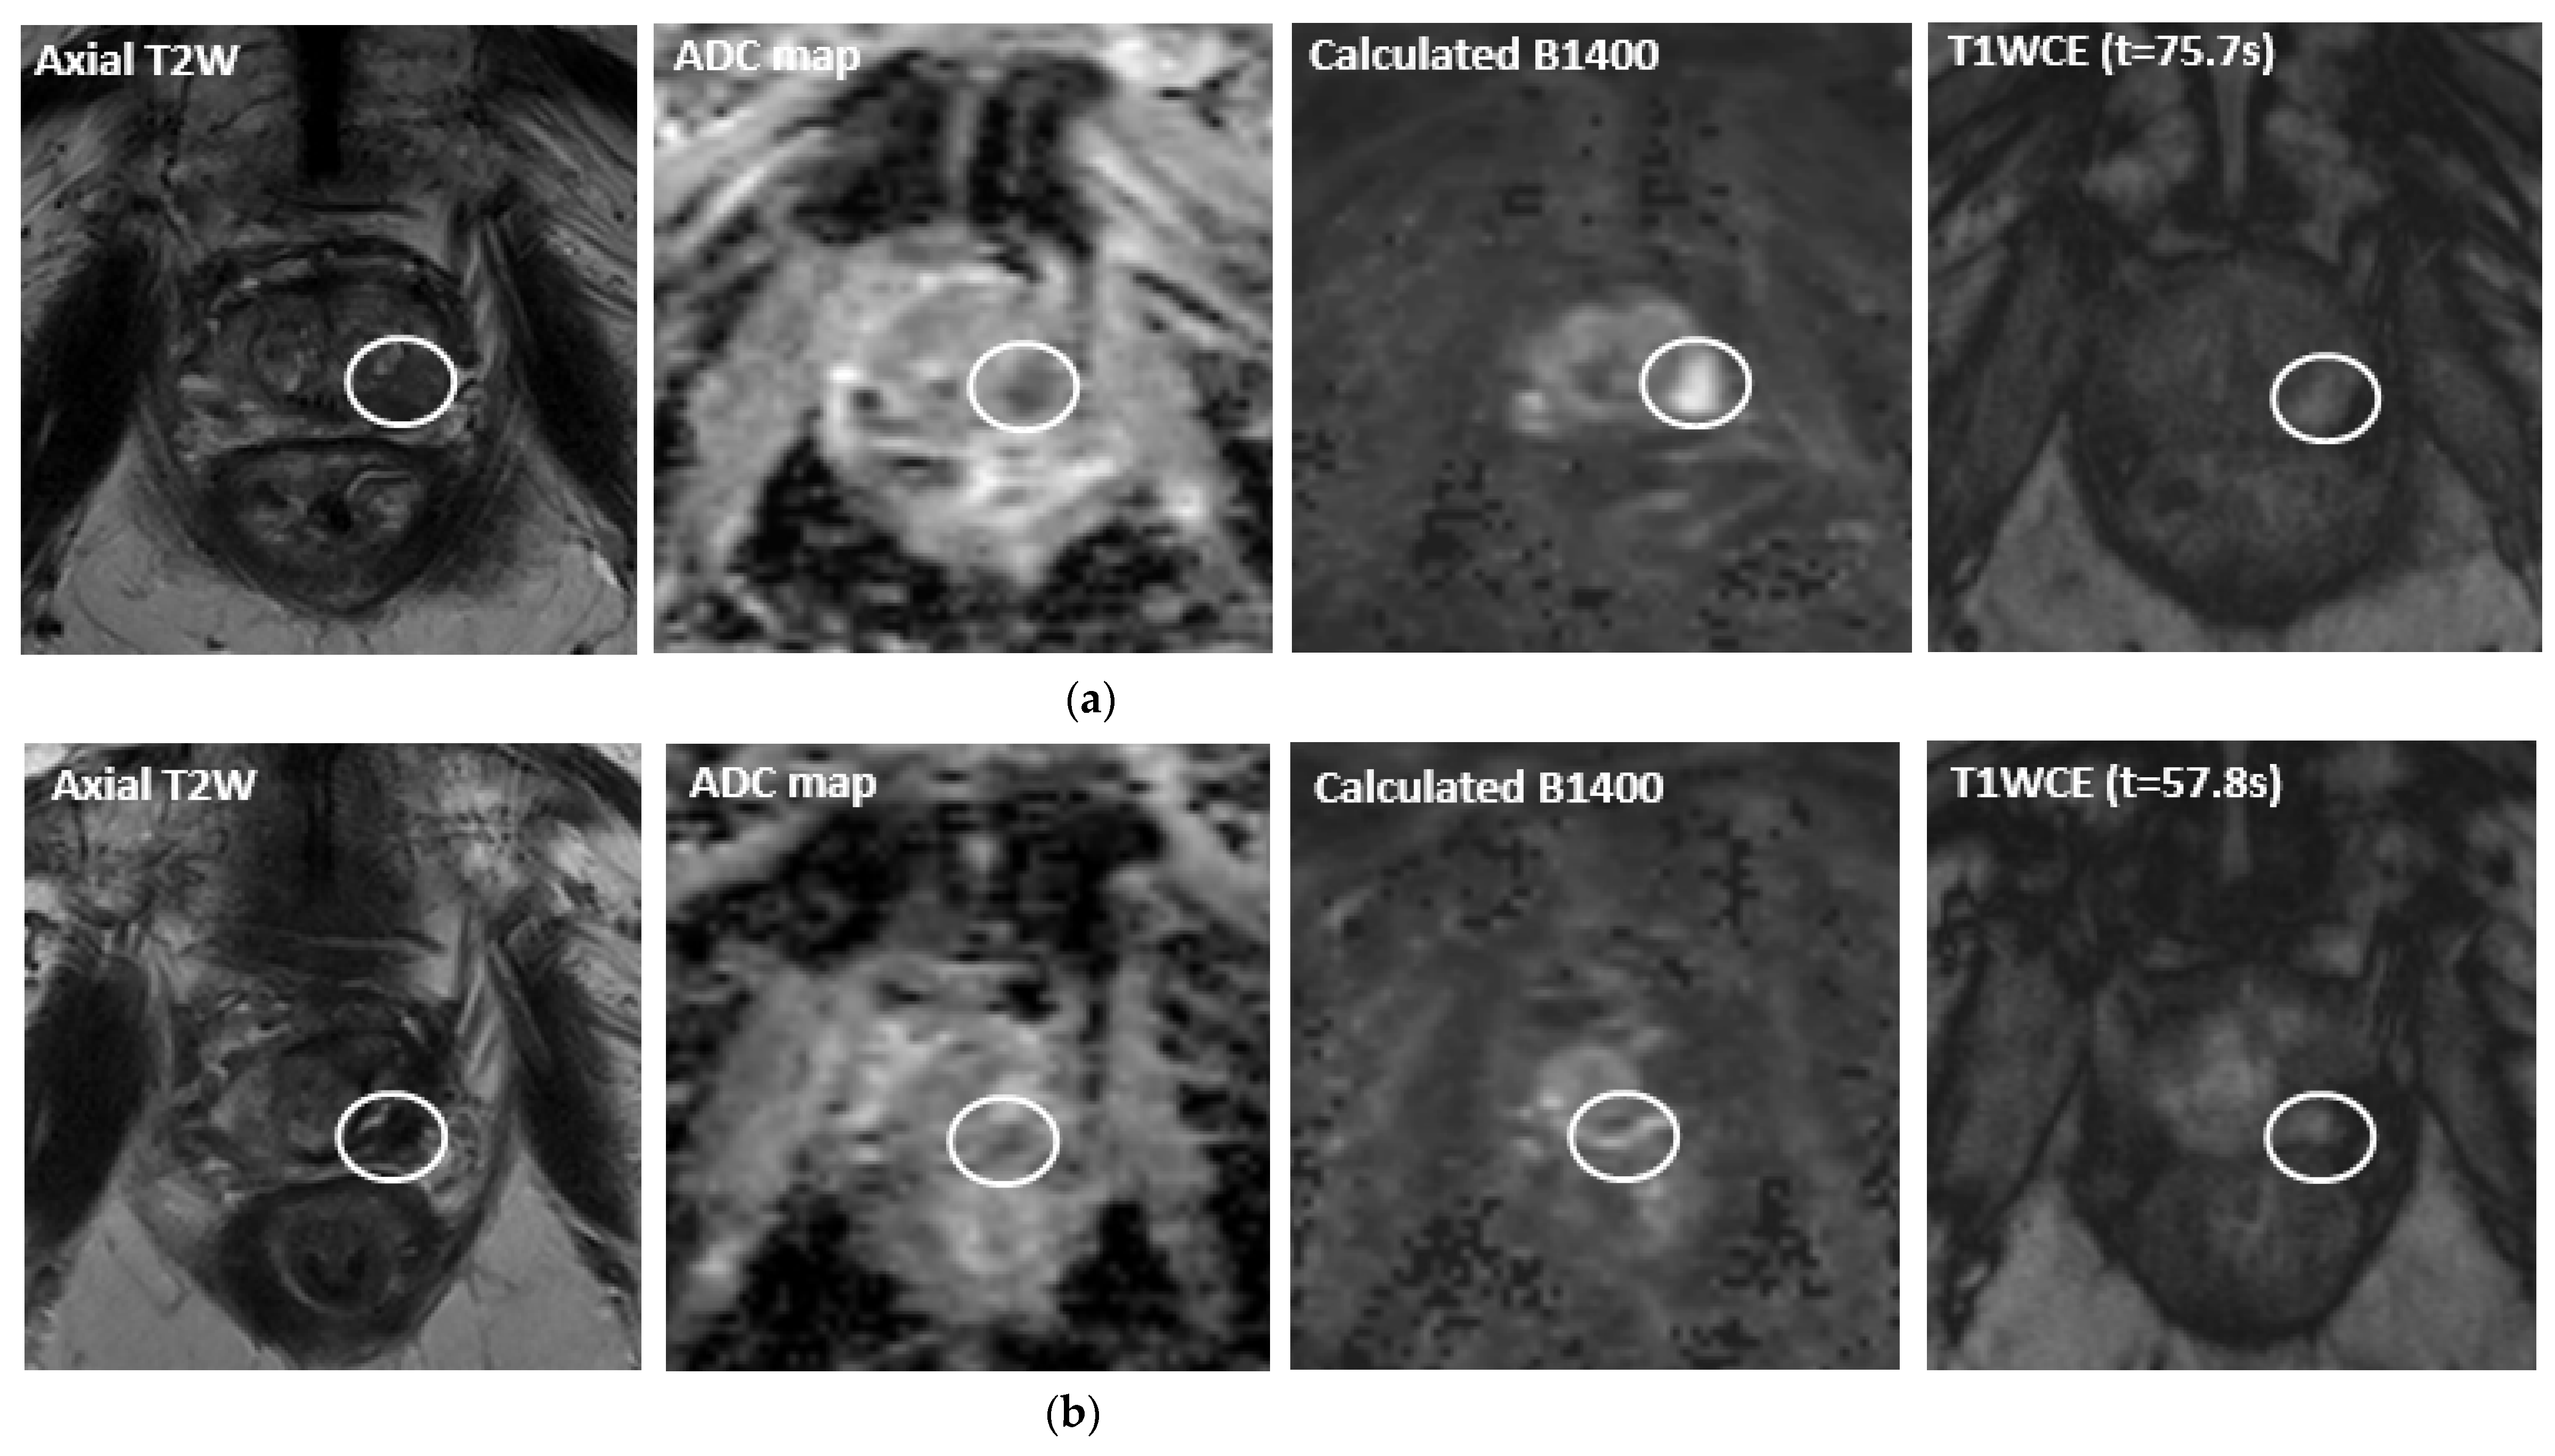

- Chopra, R.; Burtnyk, M.; N’Djin, W.A.; Bronskill, M. MRI-controlled transurethral ultrasound therapy for localised prostate cancer. Int. J. Hyperth. 2010, 26, 804–821. [Google Scholar] [CrossRef]

- Chopra, R.; Colquhoun, A.; Burtnyk, M.; N’Djin, W.A.; Kobelevskiy, I.; Boyes, A.; Siddiqui, K.; Foster, H.; Sugar, L.; Haider, M.A.; et al. MR Imaging–controlled Transurethral Ultrasound Therapy for Conformal Treatment of Prostate Tissue: Initial Feasibility in Humans. Radiology 2012, 265, 303–313. [Google Scholar] [CrossRef]

- Chin, J.L.; Billia, M.; Relle, J.; Roethke, M.C.; Popeneciu, I.V.; Kuru, T.H.; Hatiboglu, G.; Mueller-Wolf, M.B.; Motsch, J.; Romagnoli, C.; et al. Magnetic Resonance Imaging–Guided Transurethral Ultrasound Ablation of Prostate Tissue in Patients with Localized Prostate Cancer: A Prospective Phase 1 Clinical Trial. Eur. Urol. 2016, 70, 447–455. [Google Scholar] [CrossRef]

- Nair, S.M.; Hatiboglu, G.; Relle, J.; Hetou, K.; Hafron, J.; Harle, C.; Kassam, Z.; Staruch, R.; Burtnyk, M.; Bonekamp, D.; et al. Magnetic resonance imaging-guided transurethral ultrasound ablation in patients with localised prostate cancer: 3-year outcomes of a prospective Phase I study. Br. J. Urol. 2020, 127, 544–552. [Google Scholar] [CrossRef]

- Klotz, L.; Pavlovich, C.P.; Chin, J.; Hatiboglu, G.; Koch, M.; Penson, D.; Raman, S.; Oto, A.; Fütterer, J.; Serrallach, M.; et al. Magnetic Resonance Imaging-Guided Transurethral Ultrasound Ablation of Prostate Cancer. J. Urol. 2021, 205, 769–779. [Google Scholar] [CrossRef]